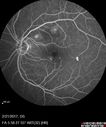

67 year old african american male with : Blurred Vision OD. Duration of Problem: 4-6 weeks. VA OD: Dcc20/32+1 NccJ5 VA OS: Dcc20/16-2 NccJ1+ There are pockets of subretinal fluid in both eyes.